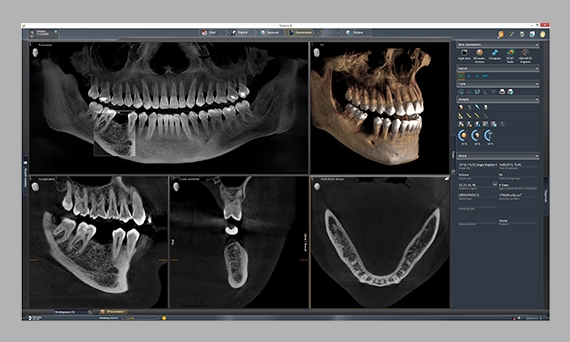

在灯箱中,您可以同时比较2D和3D图像、内窥镜画面和面阵扫描数据。

Sidexis 4数字灯箱灵活性强,可在软件界面上无缝显示所有图像类型。所有2D、3D和口内图像都可以同时处理和查看,以确保所有图像数据都可用于诊断过程。例如,可以对口内图像和3D扫描进行快速确切的交叉比较,从而极大简化诊断和治疗计划过程。因此,从患者咨询到治疗计划和模拟,这款直观的软件为您的诊断提供了理想的条件。

作为一个用户,您可能会问为什么此工具不总是实用,其实“比较”功能在软件中很有用:在比较窗口中,可以同时评估多个图像。

Sidexis 4直观的用户界面和显示器可以显示各种图像,例如口内图像、2D全景图像和3D图像。与其他软件不同,它可以提高您的诊疗效率和诊断准确性。登士柏西诺德的解决方案可让您针对多种不同的情况给出治疗计划,并为个别患者制定治疗方案。